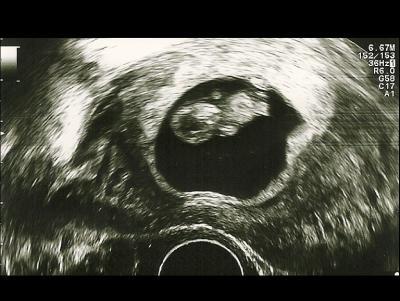

Hallo zusammen, ich war heute auch mal wieder beim FA bzw. nochmal im KiWuCentrum. Unser Würmchen ist zeitgerecht entwickelt, SSL von 2,7 cm entspricht genau SSW 9+2. Bin wieder mal sehr erleichtert und hoffe jetzt, dass die nächsten drei Wochen schnell vorbei gehen. LG und euch allen einen schönen Abend!

Bild zu War heute auch beim FA - Forum für April - Mamis

Tolle News! Freut mich sehr zu lesen, dass alles gut ist und das Bild ist ja so was von süss Ich darf das nächste mal auch bei 9+2 zum FA und hoffe sehr auf so gute News wie du und ein so tolles Bildchen!!!

Danke euch. Ich fand das Ultraschallgerät auch super. Die Bilder waren gestochen scharf, noch besser, als es auf dem Foto zu sehen ist. Wahnsinn, was es da für Unterschiede gibt. @keinnamemehrfrei: Also bei mir ist es so, dass die Angst mit jeder Schwangerschaft schlimmer wird. Zwar hab ich irgendwie ein gutes Gefühl, aber ich weiß halt viel mehr als bei meiner ersten Schwangerschaft. Bei meiner zweiten war ich auch noch entspannter, bis sie in einer FG endete. Seitdem ist es echt kaum auszuhalten. Aber irgendwie schaffen wir das schon. :-)